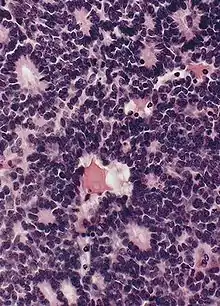

Structure of a Homer Wright pseudorosette

Homer Wright pseudorosette

A Homer Wright pseudorosette is a type of pseudorosette in which differentiated tumor cells surround the neuropil.[15] Examples of tumors containing these are neuroblastoma, medulloblastoma, pinealoblastoma, and primitive neuroectodermal tumors of bone. Homer Wright rosettes are considered "pseudo" in the sense that they are not true rosettes. True rosettes are Flexner–Wintersteiner rosette, which contain an empty lumen. Homer Wright rosettes contain abundant fibrillary material. They are named for James Homer Wright.